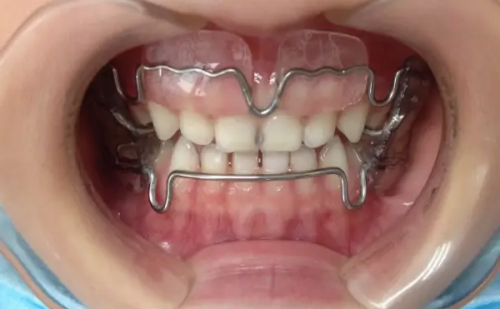

常州北极星口腔陶瓷自锁矫正项目的核心技术优势在于其成熟的医疗团队和高端设备支持。医院汇聚了一大批经验多的正畸医生,他们对于精细的牙齿矫正手术游刃有余,能够精细判断牙槽骨的健康状况,为每位患者选择更适宜的矫正方案。矫正过程注重稳、准、快,大大缩短了患者的痛苦时间和整体治疗周期,术后修复速度显著提升,让您尽快重获理想笑容。

设备方面,医院配备数字化口腔全景机和口腔CBCT等精良仪器,能清晰捕捉口腔内部的每一个细微角落,为医生诊断提供无比精细的影像资料。即使是微小的龋齿或隐藏的牙根问题,也能被及时发现和处理。口腔CBCT进行三维立体成像,使得矫正方案的制定更加科学合理,确保每一副牙套都能精细推动牙齿移向预定位置,更终实现美观与功能兼备的矫正成效。